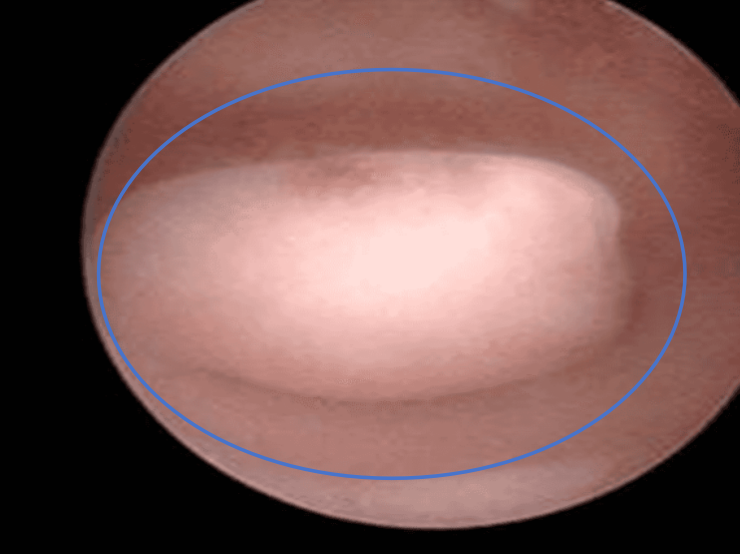

从上面的第一张图可以发现

子宫内壁应该是光溜溜的

而内膜息肉就是宫腔里

多长出来的一团肉

它可以不止一个还可能会有多个

但宫腔镜检查是比较准确的方式

可以直接观察到子宫内膜的情况

并可以进行组织活检

以确定息肉的性质